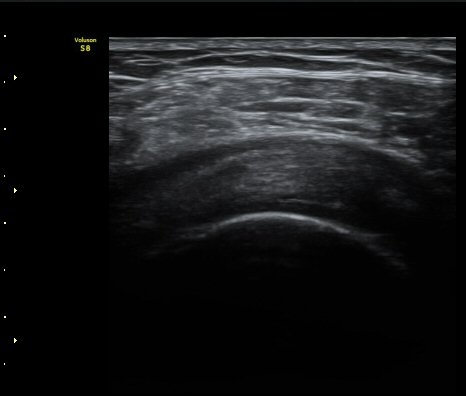

°Ë»ç¿¡¼­ Ç÷·ùÁõ°¡´Â °üÂûµÇÁö ¾Ê´Â´Ù(±×¸² 1, 2).   À̵ιڱ٠¾Æ·¡ Ⱦ´Ü¸é°Ë»ç¿¡¼­

°üÀý³» ¼ö¾×Àú·ù´Â ¶Ñ·ÈÇÏÁö ¾Ê´Ù(±×¸² 3). ±Ø»ó°Ç Á¾´Ü¸é°Ë»ç¿¡¼­ Á¡¾×³¶³» ¼ö¾×